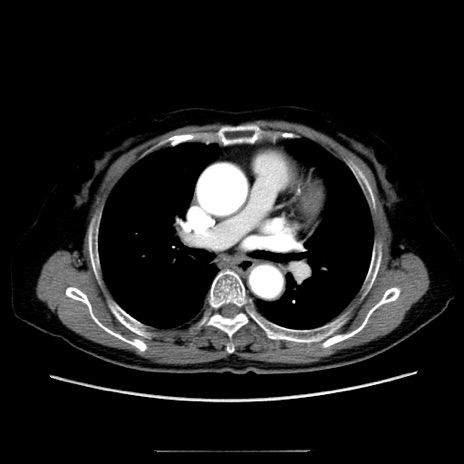

症例5(横断像)

【症例】70歳代女性

【主訴】お腹が張る

【現病歴】1週間くらい前から腹部膨満の自覚あり。昨日夜から増悪したため、本日救急外来受診。

【身体所見】意識清明、BT 36.5℃、BP 165/106mmHg、HR 80bpm、SpO2 98%、腹部:膨満、軟、自発痛・圧痛なし、触診にて不快感あり、腸蠕動音:減弱

【データ】WBC 12600、CRP 1.04